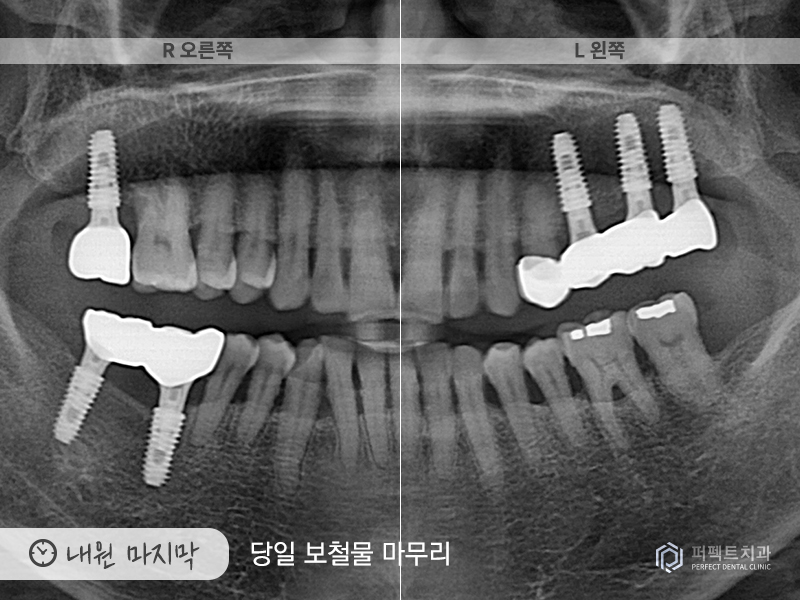

내원 4회(마지막)

3번의 내원으로 임플란트 식립을 모두 마치게 되었고, 5~6개월이 지나고 임플란트와 뼈가 다 붙은 후에 다시 내원해주셨습니다. 본원에서는 구강을 스캔하여 3d로 만드는 작업을 하고 있는데, 이 작업을 통해 당일에 보철 6개를 끼워 마무리 하였습니다.

환자분의 경우 총 임플란트 6개, 지르코니아 크라운 1개의 치료를 받으셨는데 총 5번의 내원으로 해결을 할 수 있었습니다.